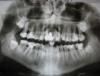

nikita10007 Опубликовано 6 мая, 2011 Поделиться Опубликовано 6 мая, 2011 (изменено) Рекомендовали удалить верхние шестерки и семерки. Неужели это необходимо? Буду признательна за ваши советы. Что делать и в каком порядке по срочности? Изменено 6 мая, 2011 пользователем nikita10007 Ссылка на комментарий

juli63 Опубликовано 10 мая, 2011 Поделиться Опубликовано 10 мая, 2011 вас беспокоят эти зубы на данный момент? 8(зубы мудрости)-совсем не нравятся, хоть и не прорезались. похоже проблемы с пародонтом. нужно перелечивать каналы в этих зубах и на нижней челюсти тоже Ссылка на комментарий

Bier Опубликовано 10 мая, 2011 Поделиться Опубликовано 10 мая, 2011 Это я на консультации предложил удалить эти зубы доктора, а вас не смущает карман до апексов у 26,27 ??? На мой взгляд однозначное удаление. что касается 16,17 - пациентке было сказано, что лечение возможно, но без гарантии, а стоимость его сопоставима или выше, чем имплантация. Др.Албан - как лечение каналов 26,27 повлияет на пародонтологическую картину в данной ситуации? Ссылка на комментарий

juli63 Опубликовано 10 мая, 2011 Поделиться Опубликовано 10 мая, 2011 Вы держали пациента в руках , Вам виднее. честно говоря, долго см на на обл. 26-27 и понадеялась, что это качество снимка не очень ... если карман до апекса-это явно не жилец. тут не то что "без гарантий", а "полный абзац". Ссылка на комментарий